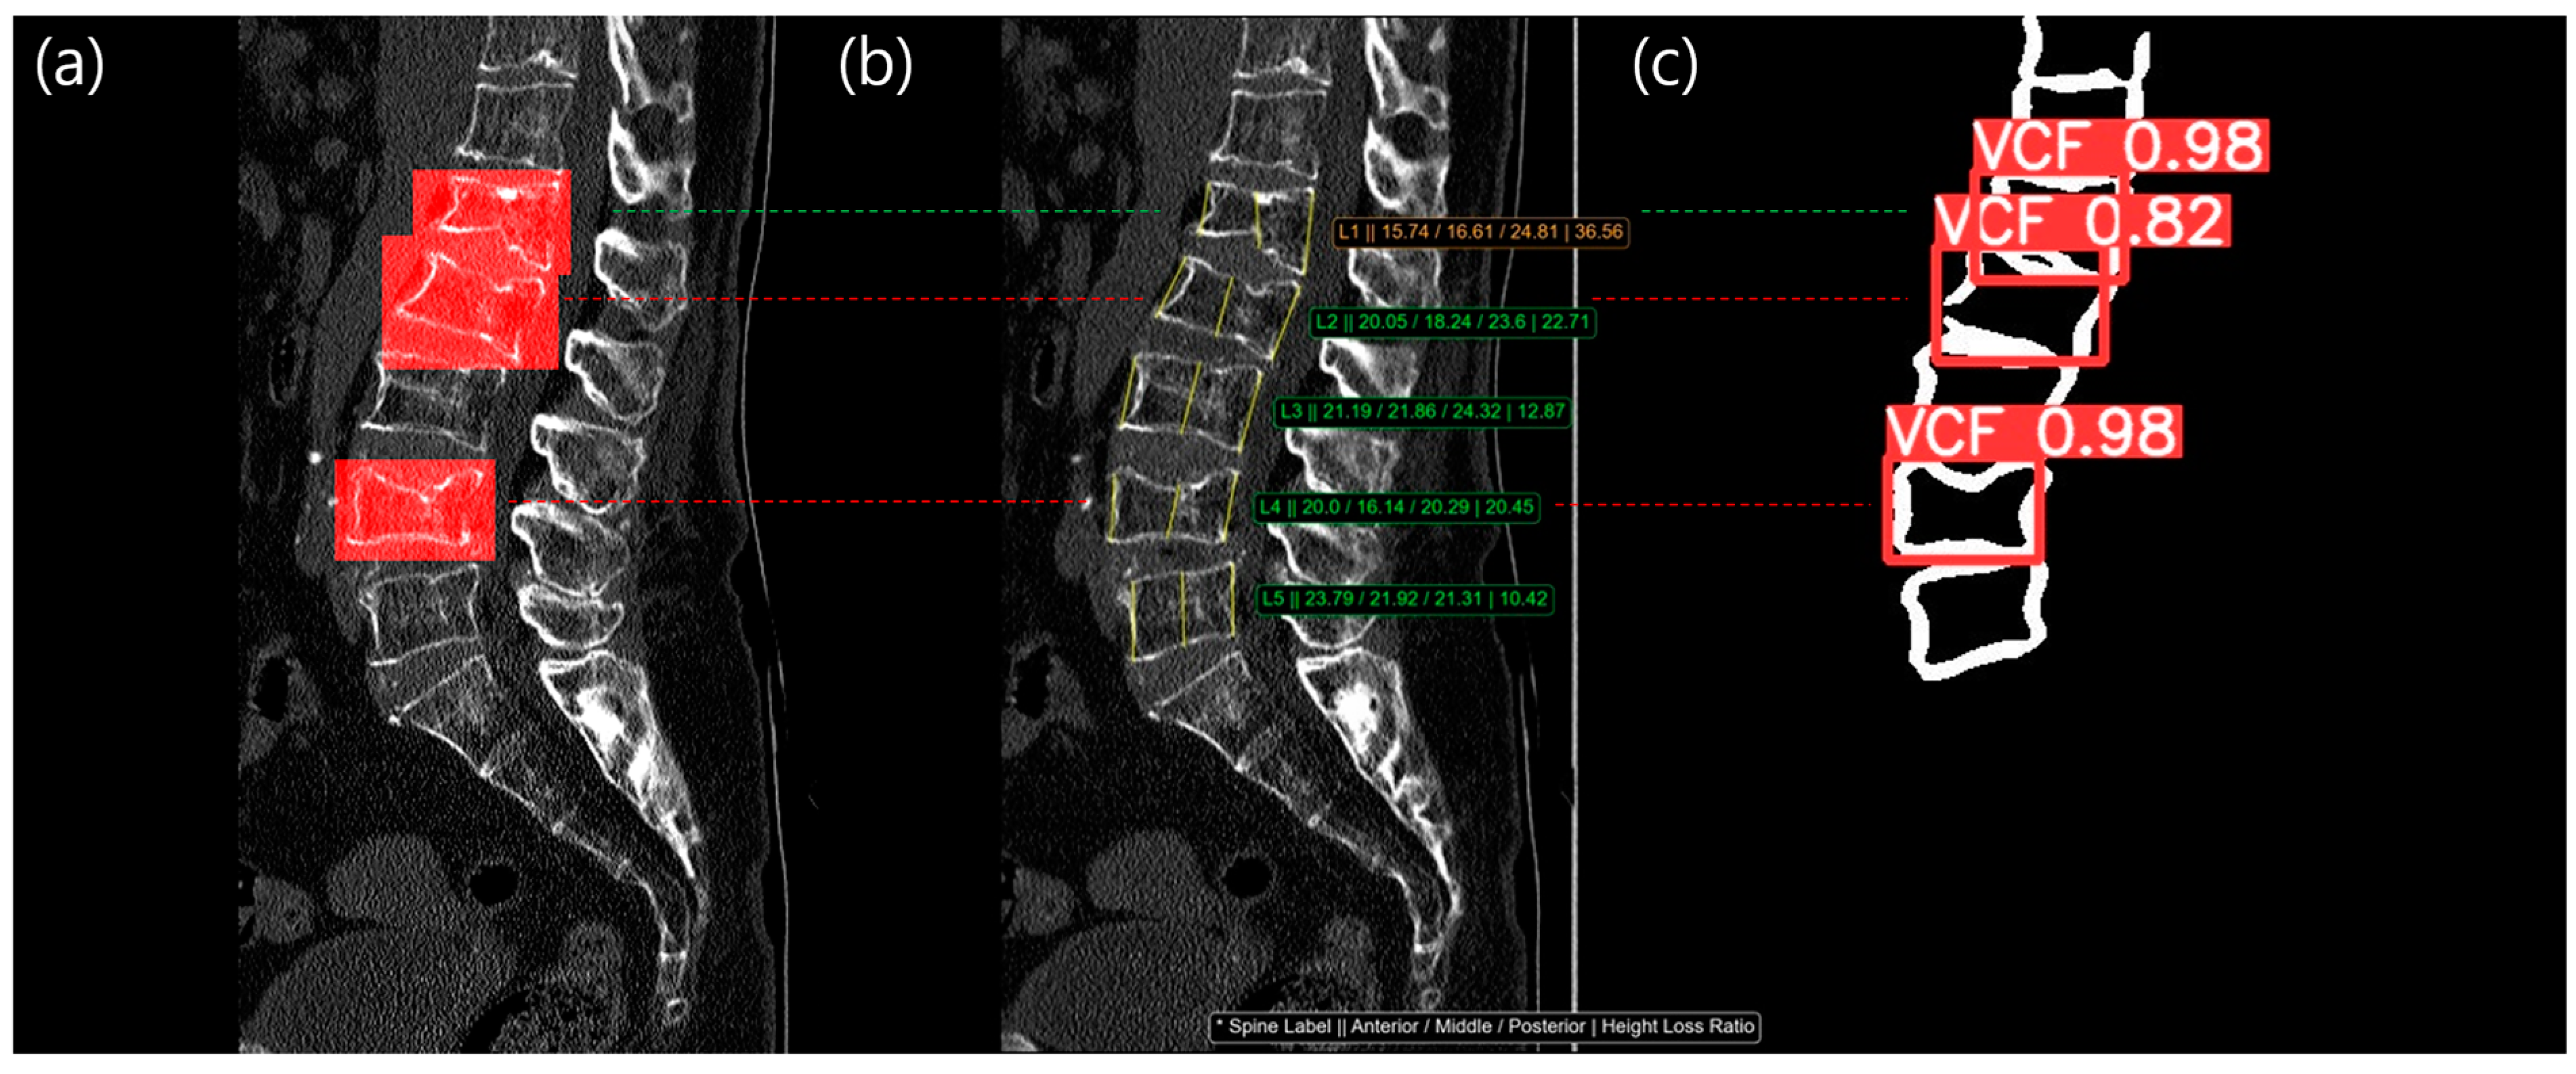

Figure 6 and Figure 7 showed example cases for Methods 3 and 4. The left image shows a filled red bounding box, representing the reference standard from a radiologist, overlaid on the patient’s CT images. The middle image shows the three main vertebral heights overlaid on the patient’s CT images. The right image shows the VCF detection result, with the confidence score overlaid on vertebral contour mask images. As shown in Figure 6, L2 and L4 were labeled as a VCF, but the HLR was normal, so it was not detected using method 1. However, the contour-based detection model was able to identify the VCF at L2 and L4 with a high confidence score (0.82 and 0.98, respectively), allowing Method 3 to detect the previously missed VCF case. In Figure 7, there was no red bounding box on the L3 vertebra, indicating that it was normal. However, the HLR of L3 was 32.05%, classifying it as a moderate VCF based on the Genant classification. The detection model also skipped L3, meaning Method 4 was able to identify more normal cases.

Figure 6.

The result images of our study: (a) Chronic VCF reference standard labeled from radiologist; (b) HLR measurement, Method 1, result. The consecutive values in the image, indicated with an * symbol, were spine label, anterior height, middle height, posterior height, and height loss ratio; (c) VCF detection, Method 2, result from vertebral contour. At L2 and L4 level (red dotted line), HLR was normal but VCF detection model was able to locate the VCF with a high confidence score (0.82 at L2 and 0.98 at L4). The green dotted line was TP in both Method 1 (b) and Method 2 (c). The red dotted line was FN in Method 1 (b) but TP in Method 2 (c).